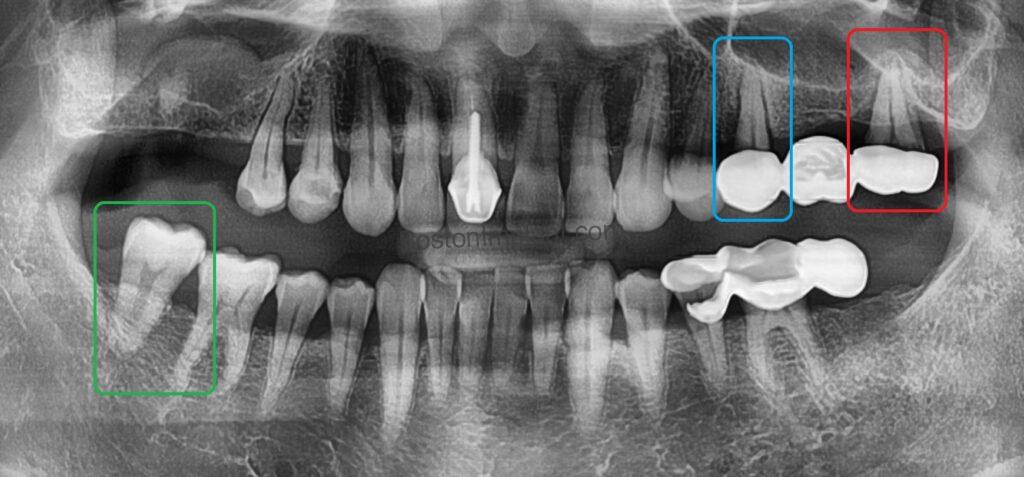

A 48-year-old gentleman sought relief at our Boston practice from persistent dental discomfort. Ten years prior, the loss of two upper left molars had understandably led him to favor his right side for chewing. This long-term compensatory habit resulted in significant strain and subsequent pain on his upper right side – a common scenario where patients inadvertently compromise healthy teeth by overcompensating for missing ones. In this particular case, despite our efforts, an additional upper right tooth required extraction (marked in red), though we successfully preserved another (marked in blue). Furthermore, the patient presented with severe pneumatization of the maxillary sinus (thinning of the remaining maxillary bone), necessitating a complex bone grafting procedure known as a lateral sinus lift. (For further information on this procedure, please refer to our ‘Sinus lift blog’.)

We also observed an issue on his left side. The lower left posterior tooth (marked in green) had supra-erupted, positioned higher than its adjacent teeth. This phenomenon occurs due to the absence of an opposing tooth. Teeth naturally continue to erupt until they meet an antagonist, counter tooth. Without this opposing force, the tooth will continue to move. This is a common finding in patients who do not seek timely treatment after tooth extraction. This supra-erupted tooth required intervention, and we discussed several options: (1) Orthodontic intrusion: Utilizing orthodontic appliances to reposition the tooth. This approach requires the most time and is the most costly. (2) Endodontic treatment and crown: A more immediate option involving root canal therapy to reduce the tooth’s height followed by a crown. While quicker, it necessitates the removal of vital pulp tissue and remains a significant expense. (3) Conservative odontoplasty: Selective reshaping or trimming of the tooth to eliminate the interference. This offers the most immediate and cost-effective (affordable, essentially free) solution. His final decision will be revealed later in this narrative.